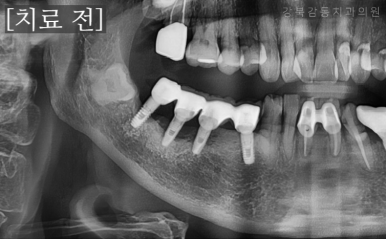

먼저 임플란트를 제거하는 수술을 진행하였습니다.

임플란트 주위염이 발생한 우측 아래 연결된 임플란트

(치과 X-ray 사진은 보통 좌우가 반대로 되어 있습니다.)

안전하게 임플란트가 제거된 모습

임플란트 제거 이후에는 다른 부위들의 치료들도 희망하셔서 반대쪽 치료 또한 진행하였습니다.

약 2개월 정도 지난 후에 잇몸이 깔끔하게 아문 상태를 확인하고,

임플란트 식립을 진행하였습니다.